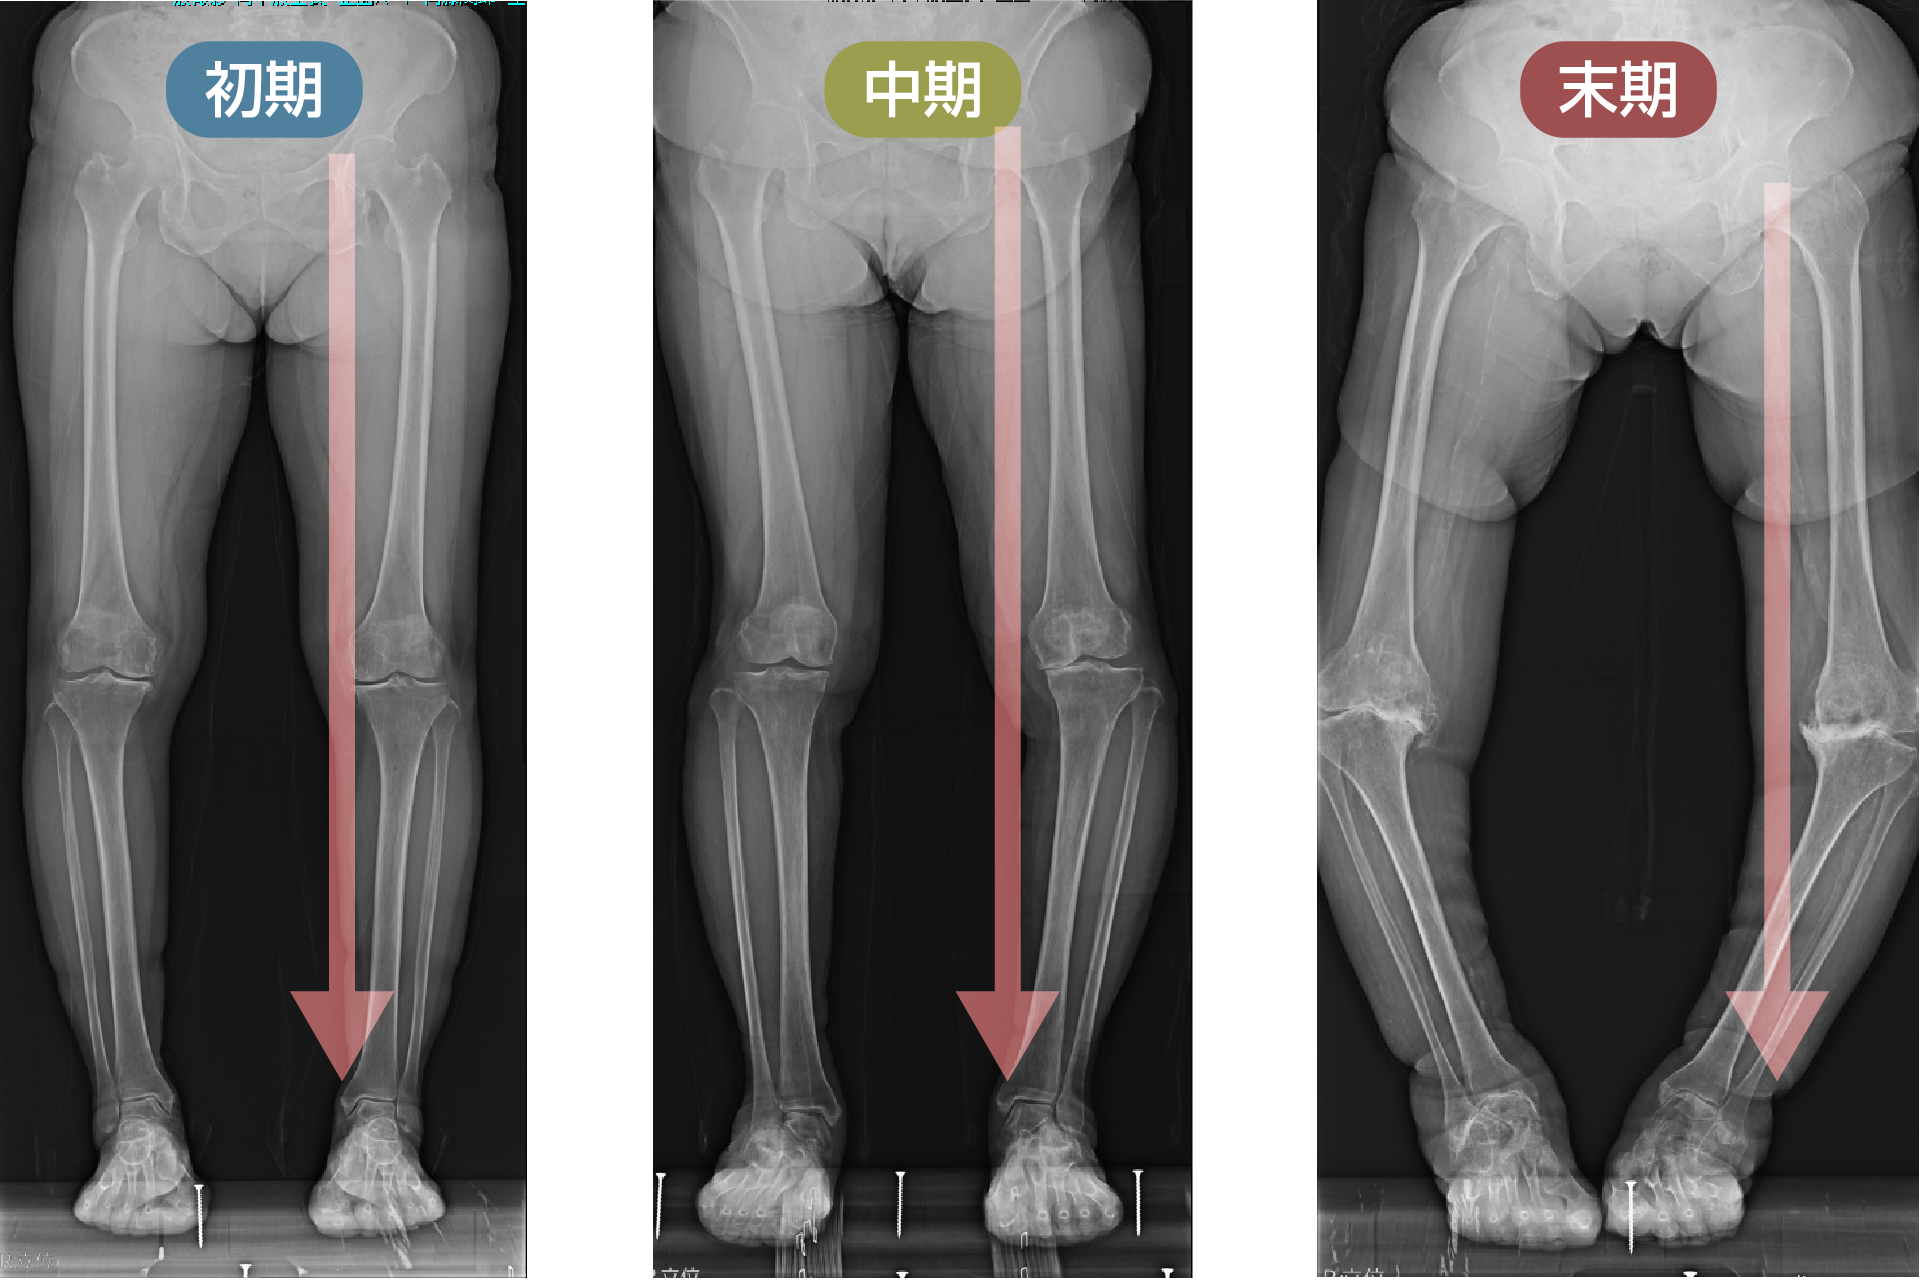

1. レントゲンの見方

ひざ関節は、大腿骨と脛骨の間の隙間の部分です。レントゲンではこの部分が隙間として写りますが、実際には関節軟骨と半月板が存在します。立位で体重をかけて撮影した場合、この隙間の広さがおおよそ関節軟骨の厚みを示すと考えてよいでしょう。この大腿骨と脛骨の隙間のうち、腓骨に近い側を外側関節、腓骨から遠い側を内側関節と呼びます。また、脛骨の中央には2つの小さな山のような部分が見えますが、ここには前十字じん帯と後十字じん帯がついています。

初期

中期

末期

※レントゲン画像左が内側、右が外側

O脚変形がみられる場合、初期のレントゲンでは外側関節に比べて内側関節の隙間がやや狭くなっています。これは内側の軟骨が少し減ってきた状態を示しています。

中期のレントゲンでは、内側関節の隙間がほとんどなくなります。この段階では、内側の軟骨が完全に失われ、大腿骨と脛骨が直接ぶつかっている状態です。低い椅子から立ち上がる際にゴリゴリという音がしたり、骨表面に髪の毛ほどの細いひび(微小骨折)が生じて強い痛みを感じるようになります。この中期変形性関節症の時期になると、痛みのために歩くのがつらくなる方が多くなります。

中期以降になると、痛み止めの薬を常用する方も増えてきます。痛みとは、ひざが脳に“骨が割れた”と知らせるシグナルであり、脳はそれを受けて修復のための炎症反応を起こし、血液を送って自己修復を始めます。ところが、痛み止めでそのシグナルを抑えたまま歩き続けると、関節の変形が進行して末期に至ることがあります。

末期では、脛骨がすり減り、大腿骨がめり込んだ状態になります。ここまで変形が進むと、ひざの中にある4つの靱帯のバランスも悪くなり、歩行が不安定になってしまいます。

平地を歩くと、ひざ関節には体重の約5倍の荷重がかかります。正常なひざでは関節のほぼ中央に荷重がかかりますが、初期の方では内側の軟骨が少し減っているため、荷重はひざのやや内側を通ります。この段階では、内側にもまだ少なからず軟骨が残っているため、骨が割れる=微小骨折を起こすことはありません。しかし、軟骨に挟まれている半月板は、隙間が狭くなっていることで損傷しやすくなります。初期のひざの痛みの多くが内側の半月板損傷によるのはこのためです。

中期の方が平地を歩いたときには、ひざ関節のかなり内側に荷重がかかります。たとえば体重が40kgの方であれば、一歩ごとに200kgの力がかかる計算になり、その重さを支えるのは曲がった下肢の骨です。一歩ごとにひざ関節が200kgの力で外側へ押し出されるため、ひざが悪くなった原因である内側の軟骨や骨はさらに損傷していきます。半月板は本来の位置を保てず、内側へ脱臼しています。

末期の方が平地を歩いたときにも、荷重はひざ関節からさらに離れた内側を通過します。その結果、荷重を支えるひざは外側へどんどん曲がり、内側の損傷部がさらに悪化していきます。このようにして、ひざの変形は進行していくのです。